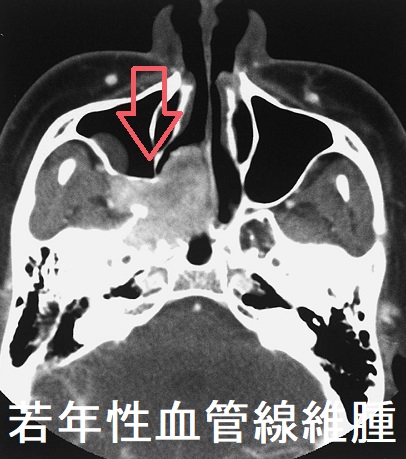

若年性血管線維腫(juvenile angiofibroma)は10-18歳の男子に多く、上咽頭に好発する極めて血管豊富な良性腫瘍で、成人すると増殖が止まります。良性腫瘍なのに、局所浸潤が強く、再発率も高いのが特徴です。

若年性血管線維腫の

- 内視鏡所見は、表面平滑で血管に富んだ腫瘍

- 副鼻腔造影CTは、造影される浸潤性腫瘤

- 確定診断は組織生検だが、大出血の危険があるため行わない事もある。所見は、小血管と線維組織。

若年性血管線維腫は出血量が多いため、良性でありながら手術による摘出が難しく、動脈塞栓後手術・ホルモン療法・放射線治療などが行われ、放射線誘発性甲状腺がんの問題があった[Laryngoscope. 1984 Dec;94(12 Pt 1):1599-605.]。